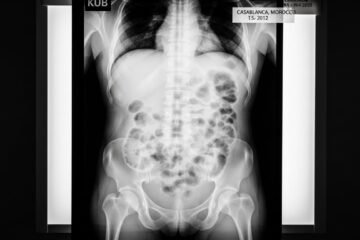

Radiographie de l’Abdomen Sans Préparation au Maroc : Guide Complet pour Patients

Votre médecin vous a prescrit une radiographie de l’abdomen sans préparation et vous vous posez mille questions ? Combien cela va-t-il coûter ? Faut-il vraiment être à jeun ? L’examen est-il douloureux ? Vous n’êtes pas seul. Chaque jour, des milliers de patients marocains se posent les mêmes questions avant leur premier ASP (Abdomen Sans […]